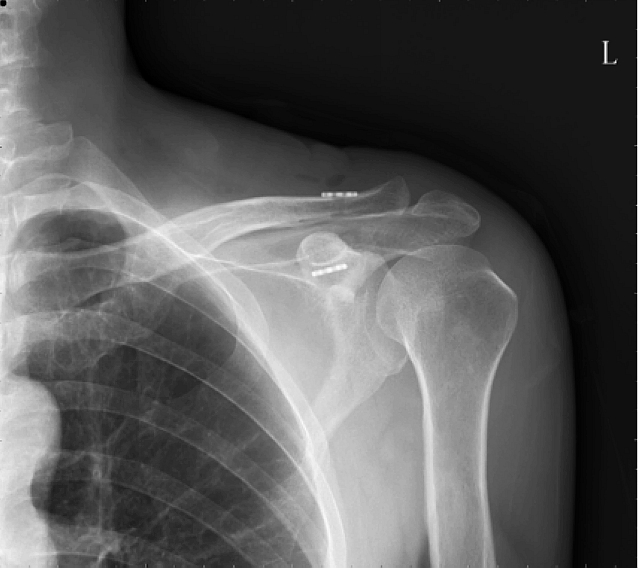

术中C臂透视

可调节带袢钢板有限切开内固定术后